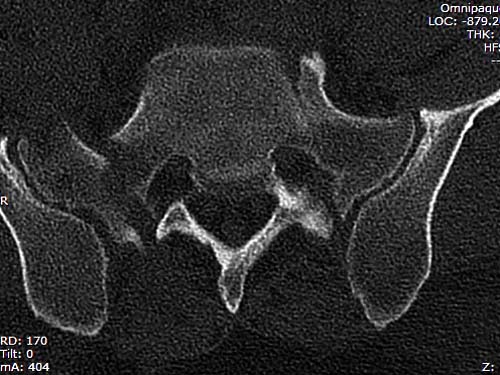

КТ, при детальном рассмотрении виден перелом задних отделов крыла подвздошной кости

складывается впечатление о переломе задних отделов подвздошной кости слева через КПС, ости остались с крестцом (надо внимательно поразглядывать КТ). В этом случае IS винты или какие-нибудь дистантные позвоночно-тазовые стабилизаторы - дело рисковое. Если мое предположение подтвердится,сначала IS винт справа, затем в положении на животе на тракционном столе (или чего-нибудь мудрить с вытяжением) попытаться достичь репозиции. Если удалось - через задние отделы в подвздошную кость 1- 2 6,5 мм винта= постараться 1 IS винт через передние отделы подвздошной кости. если репозиция вас устраивает- АВФ спереди.

Перелом заднего отдела крыла подвдошной кости доказывает, что задние связочные элементы подвздошно- крестцового сочленения интактны, и такой перелом известен как “Сrescent fracture’. Переломы разделяется на 4 типа, и до фиксации надо хорошо изучить топографию перелома, иначе винт может попасть в линию перелома и не удержать фиксацию.